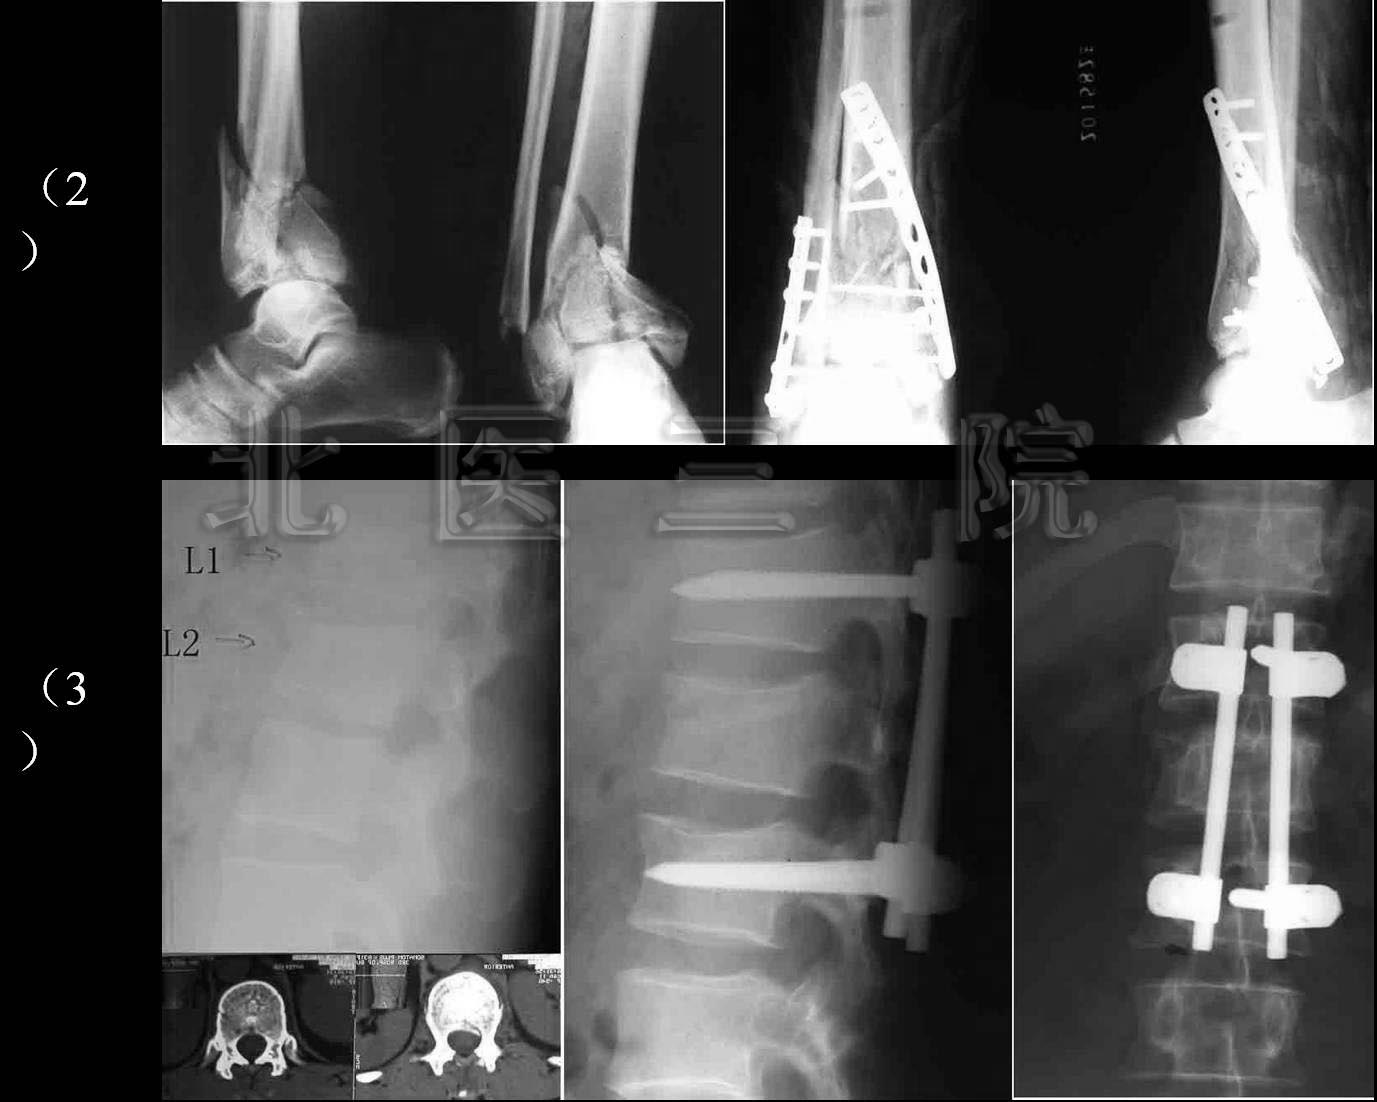

4.男,35岁,车祸致多发创伤

1)股骨上端骨折

2)胫腓骨下端粉碎性骨折

3)L1、L2骨折

图1:21岁美国大学生,车祸致颈、腰椎多处骨折,四肢不全瘫。

FIGURE 1:A 21-year-old American college student, multiple fractures

of cervical and lumber spine in a car accident, ASIA C incomplete paralysis.

图2:手术后一周下地行走。

FIGURE 2: standing and walking one week after operation

图3:手术后9个月复查

FIGURE 3: Nine months after operation